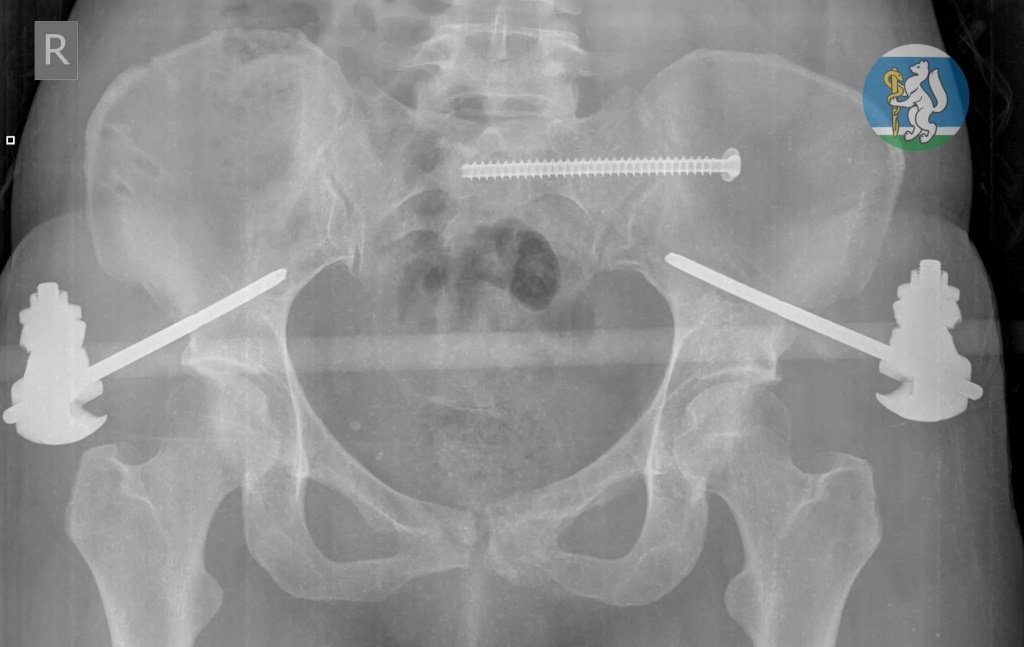

Об этой удивительной истории рассказали в свердловском минздраве. Бригада скорой помощи доставила женщину в состоянии травматического шока в профильную больницу. У пациентки диагностировали черепно-мозговую травму, повреждение шейного отдела позвоночника, множественные переломы костей таза, травму грудной клетки с повреждением легких, открытые оскольчатые переломы левой ноги. Первой задачей врачебной бригады было вывести пострадавшую из шокового состояния, зафиксировать переломы, остановить кровотечение. Несколько часов молодая женщина провела в операционной на грани жизни и смерти.

После экстренной операции екатеринбурженка находилась в реанимации на искусственной вентиляции легких до полной стабилизации состояния. Через полторы недели ее перевели в отделение травматологии, а еще через две недели врачи успешно выполнили операцию по частичному демонтажу аппаратов внешней фиксации и синтезу сломанных костей.